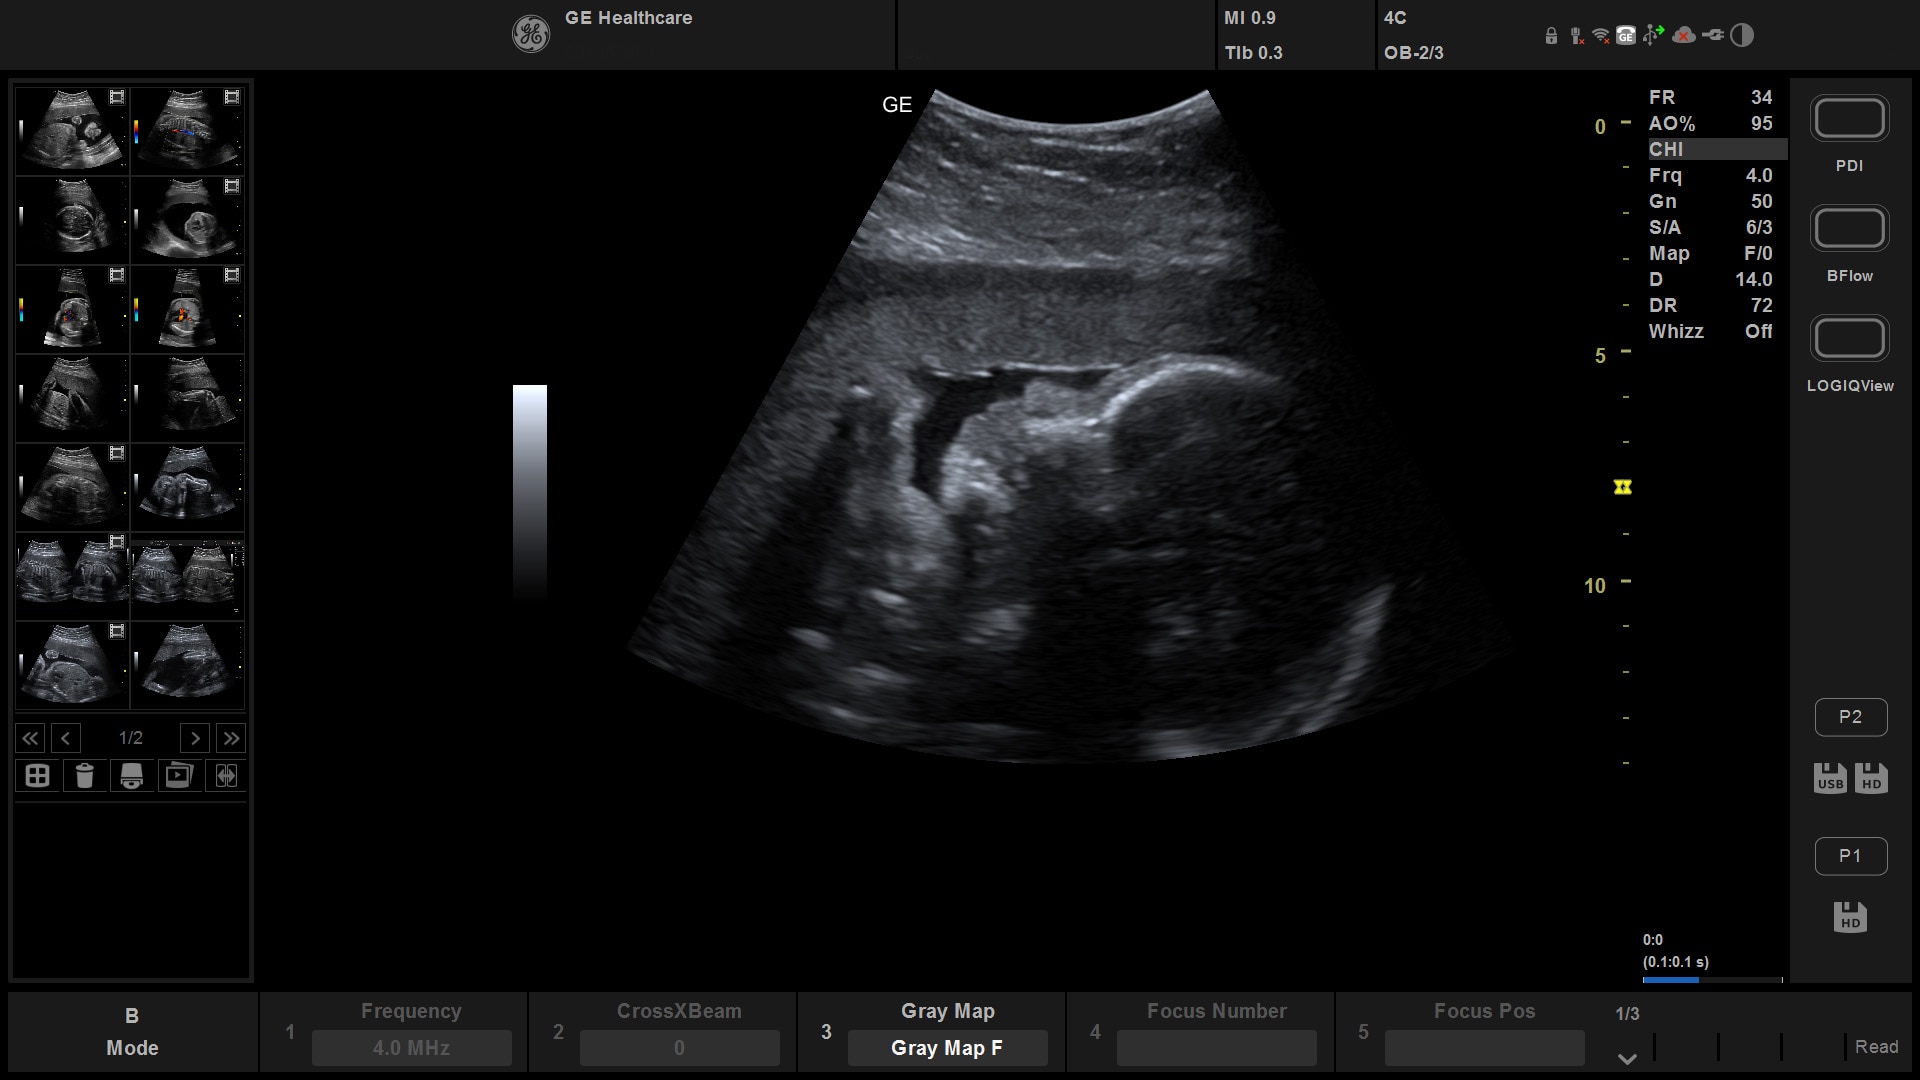

Suited for abdominal, small parts, cardiac, OB/GYN, vascular, and MSK exams

Versana Active features a wide range of advanced clinical applications and automated tools that simplify exams, streamline workflow, and enable fast, high-volume scanning to help you diagnose a wide spectrum of patient conditions.

4D¹

Aids decision making by enabling additional dimensions in real time